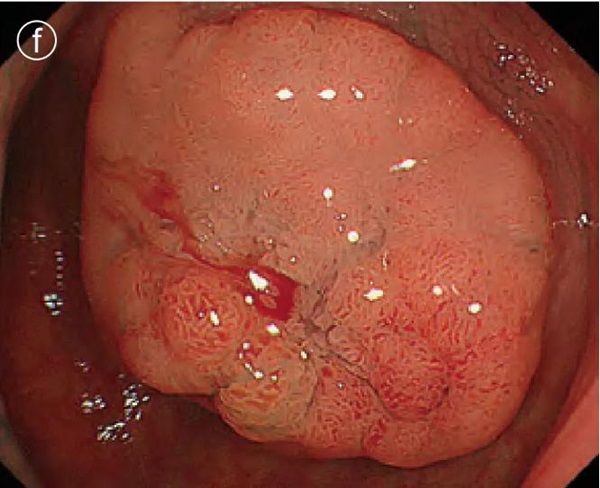

f. Local injection

Puncture and local injection were performed in the center of the lesion , resulting in a good bulge.